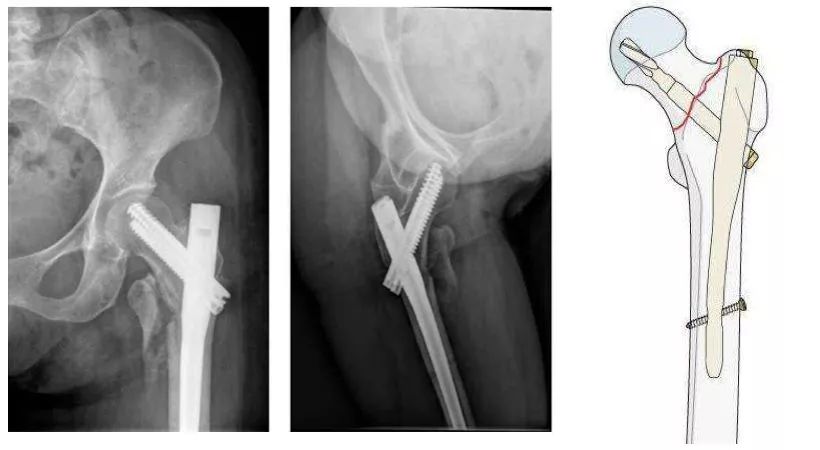

1、内固定。根据骨折情况、骨质情况选择髓内钉、钢板或螺丝钉内固定。

1、内固定:适合骨质良好的粗隆部骨折。

优点:骨折愈合后恢复到骨折前的解剖状态,闭合髓内钉技术创伤小。

缺点:骨质疏松患者内固定把持力不足,容易出现内固定剪切失效;即使固定牢固,也不能早期负重行走,恢复比较慢。

粗隆间骨折,骨质疏松,把持力不良,钉板固定,螺钉切割失败。